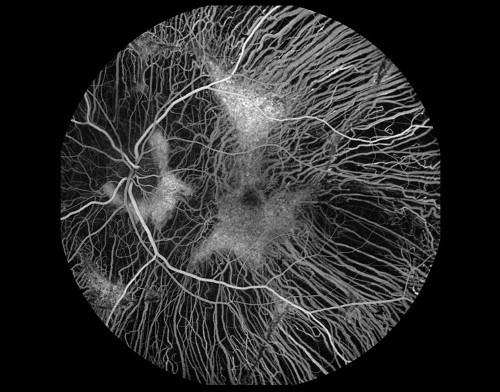

- 3. mesto v kategoriji FLUORESCEIN ANGIOGRAPHIES